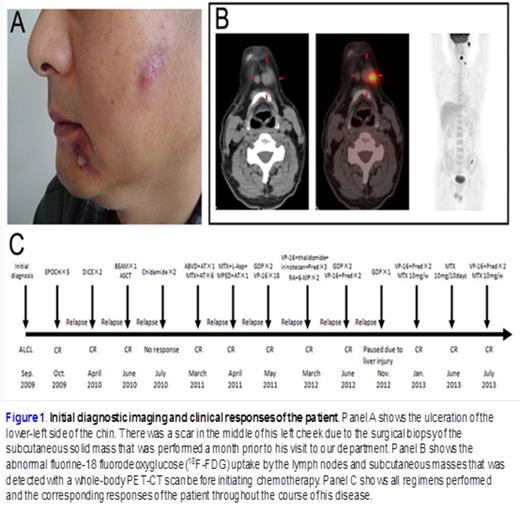

The prognosis of ALK-positive, anaplastic large cell lymphoma is usually favorable, but patients that are resistant to primary chemotherapy or who relapse early have always been associated with an aggressive clinical course and unfavorable prognosis. For a recurrent relapsing case of ALK-positive, anaplastic large cell lymphoma heavily pretreated by nearly 50 cycles of chemotherapeutic agents (Fig 1.), we developed a treatment schema of metronomically scheduled low-dose methotrexate, which successfully controlled the relapse more than 12 months (Fig. 2). The metronomic therapy that we identified from this case was an effective and economic option that caused less damage to other organs than other treatments; thus, it should be given consideration for the treatment of similar cases, especially in the setting of where the recurrence seems to be only skin disease or when other effective regimens are unavailable. Our study represents the first report of a well-documented case of ALK+ALCL which was refractory to various lines of therapy but which was subsequently successfully treated with a combination of prednisone and etoposide followed by low-dose MTX maintenance metronomic therapy.